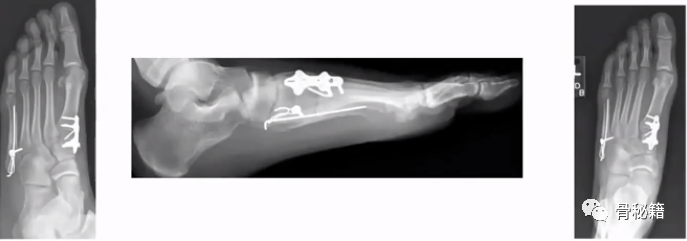

5、第五跖骨骨折